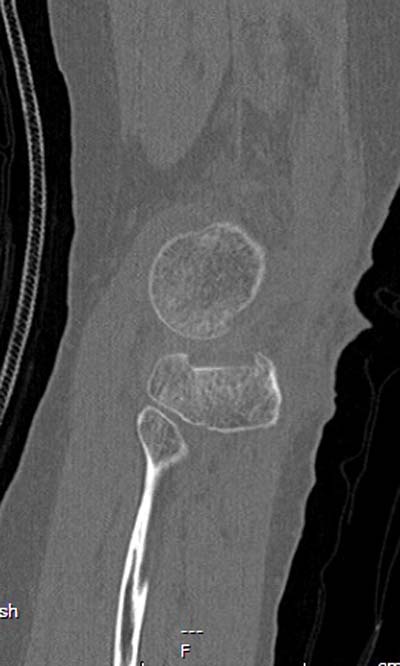

Устранение импрессии, костная аутопластика, остеосинтез опорной пластиной

оперировать вероятнее всего надо, импрессия приличная , думаю около 1,5 см, только вот она в задних отделах, преимущественно. Если ставить опорную пластину, то делать это нужно сзади, иначе никакой опорности, а задний котртекс по КТ похоже замят

задний кортекс не повреждён. Подойдёт рафтинговая пластина.

Учитывая, что у пациента молодой возраст(судя по рентгенограммам,абсолютно показано восстановление суставной линии: подменисковый доступ,подъём импренированной части мыщелка, костная аутопластика, остеосинтез, решение вопроса с мениском (шов либо парциальная резекция)).

Как подсказывают, можно с противоположной стороны приподнять сустав и заполнить костный дефект. Параллельные винты создадут достаточную опору, но иногда buttress plate за счет диафиза создает дополнительную стабильность. Структуральный материал для профилактики от раннего коллапса, и пластическим материалом служит более твердый синтетический материал (Osteoset DBM) или аутокость.

Для лечения некоторых видов центральной импрессии (Schatzker III) можно применить методику Balloon tibioplasty, которая позволяет приподнять сустав без дополнительных доступов. Для информации здесь недавний пример, дефект заполнен жидкой формой композитного материала PRO-DENSE: http://www.wmt.com/prodense/product_overview.asp